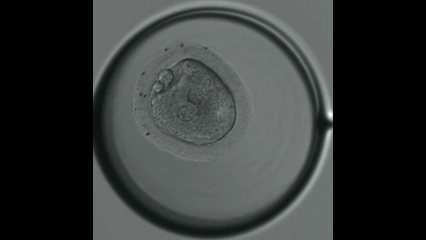

生殖医療

患者・家族様の許諾を得て掲載

体外受精・顕微授精

良好な卵子および胚(受精分裂を開始した後の卵)を得ることは、体外受精の治療において最も重要ですが、昔ながらの基本的な生理学に基づいた知識と日々最新の医学情報を得て、これらを合わせながら診療を行っています。卵巣予備能や年齢を勘案し、個人の状況にカスタマイズしますが、奈良医大産婦人科に基本となるプロトコールを作成しています。